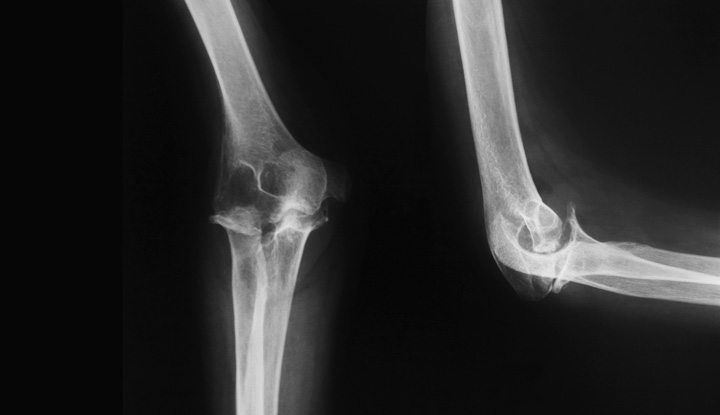

Left Elbow X Ray

File:X-ray of normal elbow by lateral projection.jpg - Wikipedia Elbow series | Radiology Reference Article | Radiopaedia.org X-ray Left Elbow Joint AP & Lateral View | Test Price in Delhi | Ganesh Diagnostic 12,736 Elbow X Ray Images, Stock Photos & Vectors | Shutterstock | Left Elbow X Ray